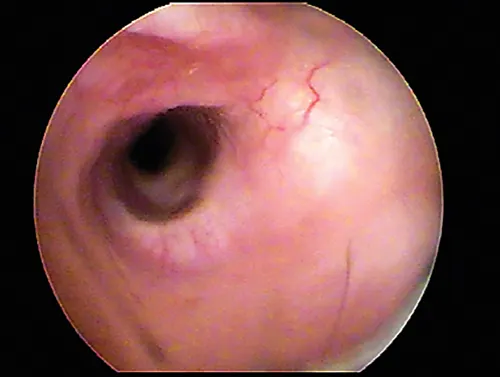

The ear canal is lined by a modified epidermis. The wide vertical ear canal contains hairs surrounded by sebaceous glands, as well as aprocrine glands unassociated with hair follicles. The normal vertical ear canal glistens because of the cerumen coating (Figure 3). On examination of the ear canal with the otoscope, the skin of the vertical and horizontal ear canals should be nonerythematous. The epithelium of the ear canal is smooth. A network of blood vessels in the dermis is present.

Otoscopic image of normal internal ear canal in a dog.

FIGURE 3

Normal canine vertical canal. Blood vessels are visible in the dermis through the thin epithelium. A glistening coating of cerumen is present on the epithelial surface.